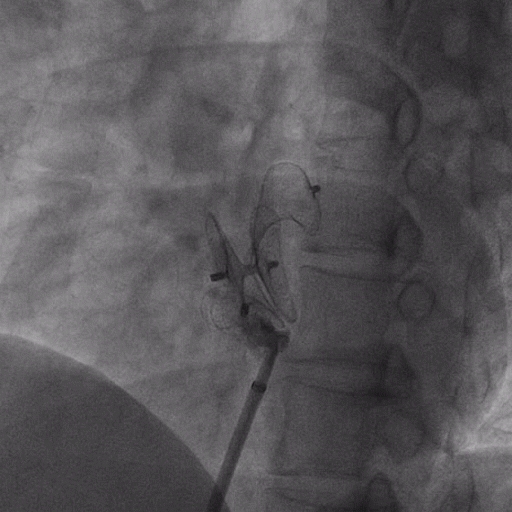

在獲得患者同意后,1月12日,尚福軍主任為患者進(jìn)行了PFO封堵術(shù)。術(shù)中造影可見(jiàn)封堵器殘余漏,尚福軍主任用精湛的技藝,順利通過(guò)封堵器殘余漏裂縫,將右心導(dǎo)管從右房送入左房,且順利到達(dá)肺靜脈;遂行卵圓孔未閉封堵術(shù)后殘余漏再次封堵;且完美釋放PFO封堵器,可見(jiàn)兩封堵器呈“馬蹄蓮”狀,再次術(shù)中造影未見(jiàn)殘余漏。